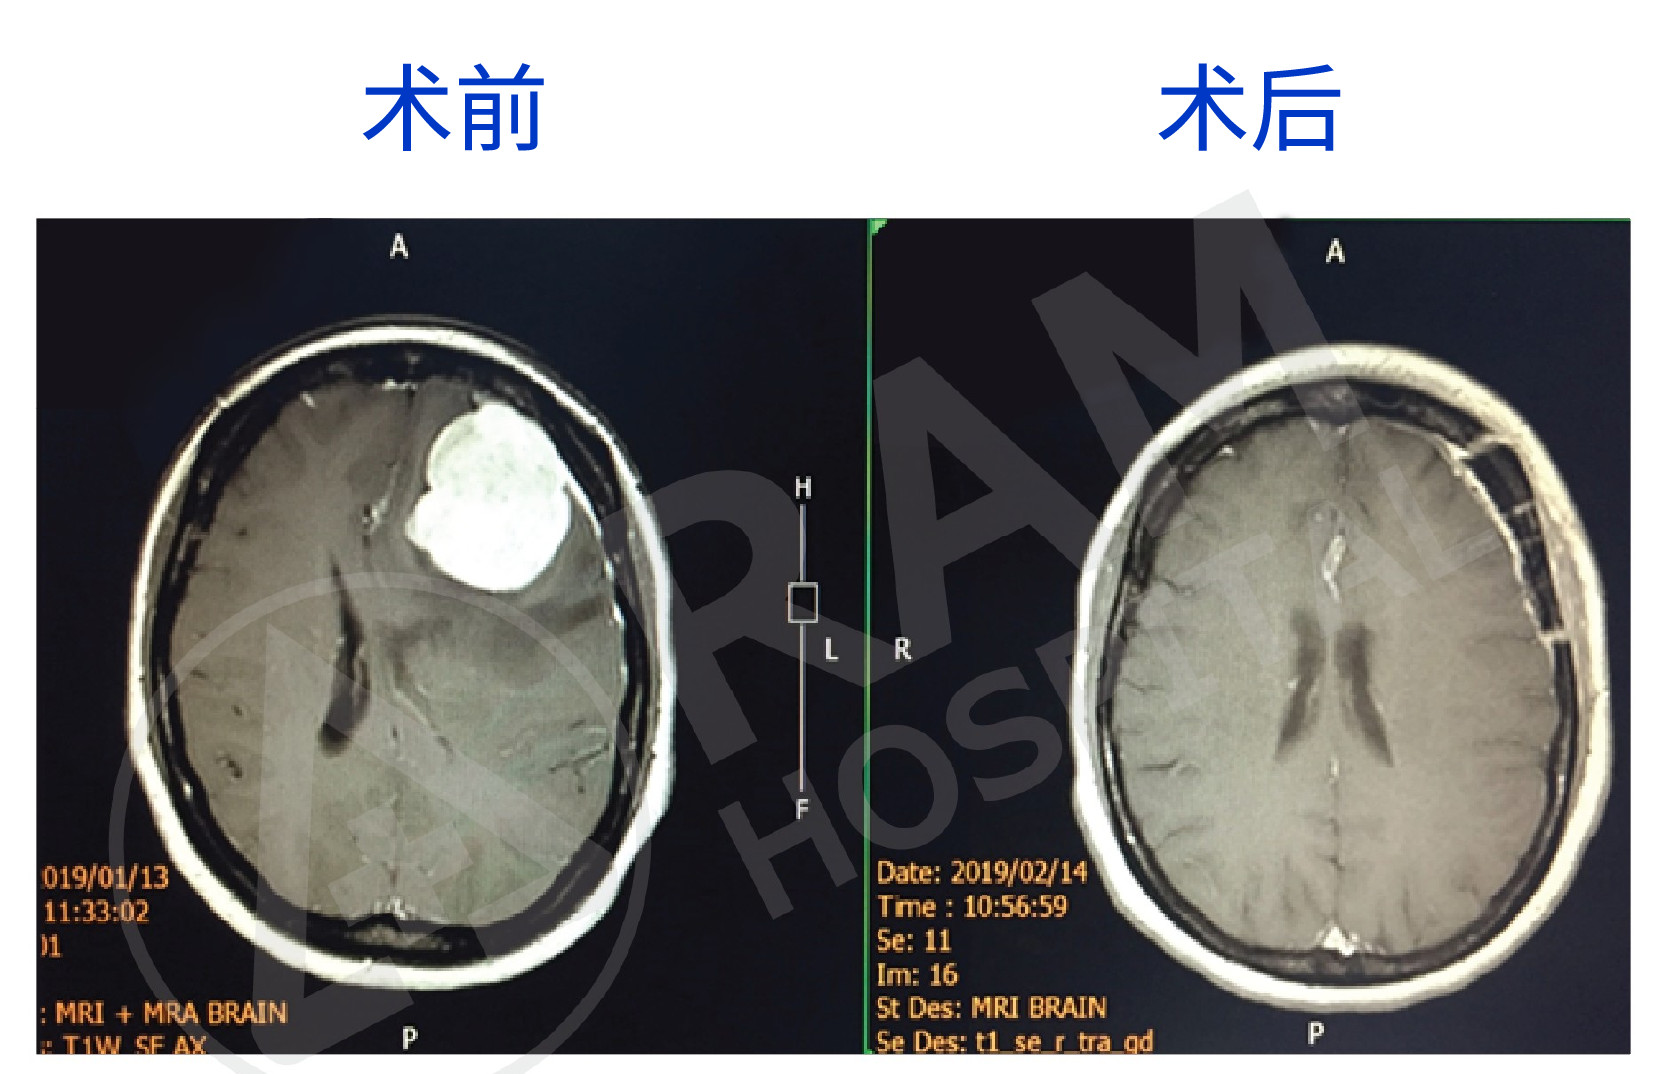

对于无需手术的脑肿瘤患者,可通过临床症状观察和磁共振成像(MRI)进行随访监测治疗。